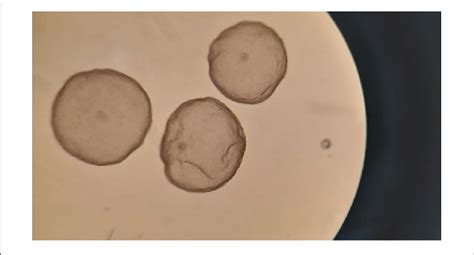

A fully Hatched Blastocyst

Source: kicchennai.com